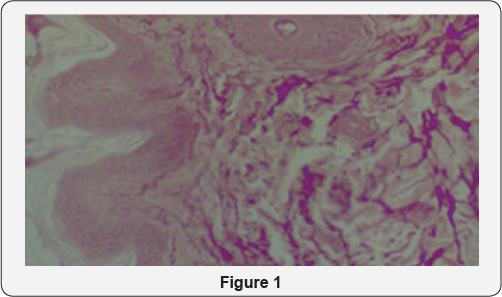

We examined and studied 347 patients who were experiencing problems as xanthelasmas (38), hemangiomas (4), eyelid cysts (20), entropion (2) ektropion (10), syrignomas (100), papillomas (100) benign nodules (45), chalazion (8) and benign tumors in difficult areas such as the gray line (20). The age range is from 25-78 years of age, smoking and non-smoking men and women. All incidents had as common fact the fear of surgery that is why the suggestive method was with Plasma Exeresis [3-6] (Figure 1).

The result in all cases is the complete sublimation of the problems from the first session, without scarring, sutures, and long recovery periods. In cases of ectropion and entropion we may need a second session depending on the degree of ectropion / entropion (2nd or 3rd degree). Using Plasma Exeresis method is effective not only because the patient avoids surgery having the same effect with less cost but also for histological reasons. Histological analyzes before and after show that in regions that was applies Plasma Exeresis, the area not only reconstructed but created and type collagen III after application [12,13] (Figure 3 & 4).